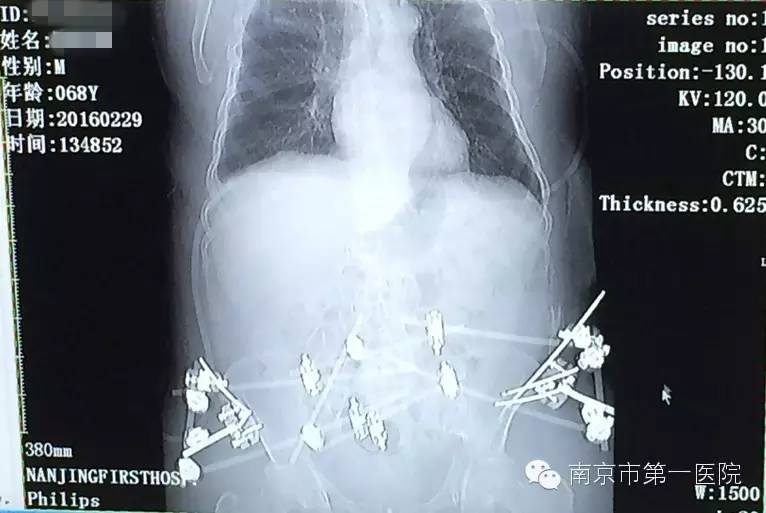

1月25日,由于车祸造成老张骨盆内有血管损伤,在他病情相对稳定后,医生准备对其造影介入手术,安置防血栓滤网,防止肺血栓再次发生。手术过程中,他又出现21日的症状,心肺复苏抢救10分钟后,终于再次将他从死亡线上拉了回来。

“老张盆骨的血管有损伤,血管壁就会很毛糙,失血性休克会导致血液流动速度缓慢,容易形成血栓,这也是老张出现危险的主要原因。心肺复苏后,随后对他进行了血栓滤网的放置,后来再也没有出现类似情况了。”郑曙云还表示,经过一系列的抢救治疗,老张已经脱离危险,情况良好,以后还能像正常人一样自理生活。

我院骨科专家梁斌接到通知后,开通多发伤绿色通道,迅速召集科内骨干医生进行术前讨论、制定手术计划。考虑到患者创伤严重、出血量大,必须最大程度地减少手术伤口,梁主任决定立刻采取微创技术进行骨盆闭合复位支架外固定术。

术中,主刀医生操作技术娴熟,争分夺秒,有条不紊地进行着各项操作。经过1个小时,手术顺利结束,成功修复了患者重度骨折的骨盆。据悉,整个手术过程中,创伤小、出血量低,切口大小也仅有1-2cm左右。